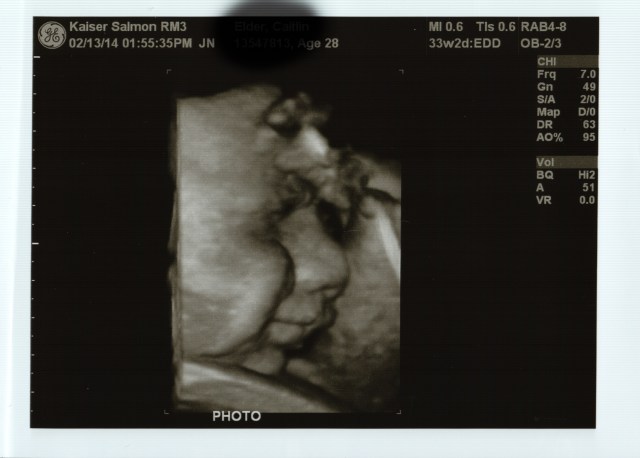

So, as promised, ultrasound photos of our handsome Little Man.

Happy face, with his hand against his forehead.

Grumpy face (or as Mo would say, “He has angry eyebrows!”).